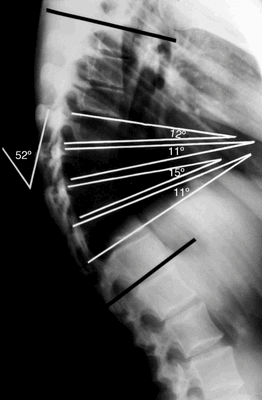

На рентгенограммах позвоночника- грудо-поясничный кифосколиоз на фоне Болезни Шейермана-Мау, угол кифоза 76° по Cobb.

При болезни Шейермана происходит структурная деформация тел позвонков и позвоночника в целом. При этом заболевании кифотический угол в грудном отделе составляет около 45-75 градусов. Кроме того, происходит клиновидная деформация трех и более соседних позвонков на 5 и более градусов. Клиновидные тела позвонков определяют природу гиперкифоза, который наблюдается при болезни Шейермана. Гиперкифоз может быть скомпенсирован поясничным или шейным гиперлордозом.

Согласно Sorenson, кифоз Шейермана характеризуется следующими критериями:

- Три или более соседних позвонков имеют клиновидную деформацию ≥ 5 градусов.

- Отсутствуют врожденные патологии позвоночника, а также его инфекционные заболевания и травмы.

Для оценки кифоза Шейермана необходимы тщательно собранный анамнез, физикальное обследование и рентгенограммы в боковой и передне-задней проекциях. Боковые рентгенограммы требуются при диагностике. Диагностическими критериями являются:

- Грубый гиперкифоз более чем 40 градусов.

- Передняя клиновидная деформация тела позвонка на 5 градусов или более (в трех или более соседних позвонках).